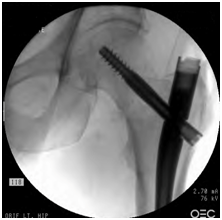

Figure 4 AP view of the left hip showing acceptable reduction and surgical fixation with an intramedullary nail.

Figure 5 Lateral view of the left hip acceptable reduction and surgical fixation with an intramedullary nail.